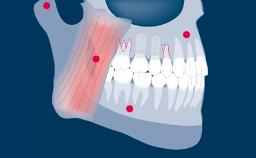

An implant abutment is the part or component that serves as support and/or retention for a dental prosthesis. The selection of the implant abutment for each individual patient case is therefore an important part of the implant-prosthodontic treatment phase. In this module, we will discuss the function of implant abutments, different implant abutment types, different abutment materials and how to select an abutment based on a prosthodontically driven process.

- define the function of implant abutments

- select abutments based on prosthodontic indications and planning